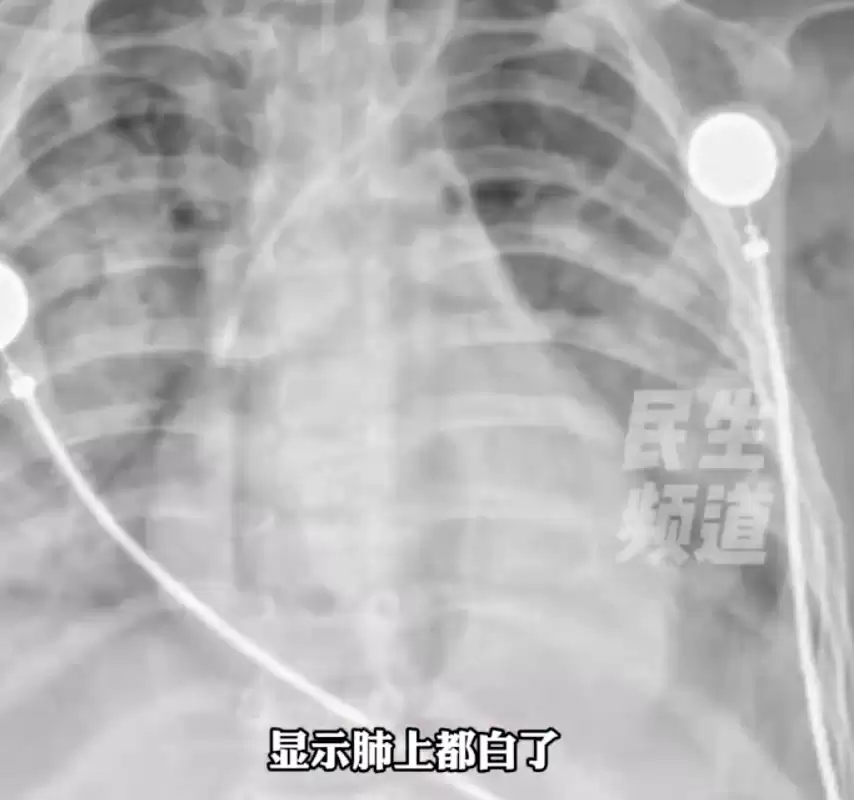

近日,河南南阳的一个1岁宝宝,因误喝10ml婴儿紫草油,吸入肺中被送进ICU抢救。据妈妈回忆,她发现宝宝误喝婴儿紫草油时,大声制止,并紧急抠嗓子催吐。“油脂吸入了肺里,形成了肺部油脂性感染。宝宝受惊呛到了,他才1岁刚学会走路,都是我的操作失误。”